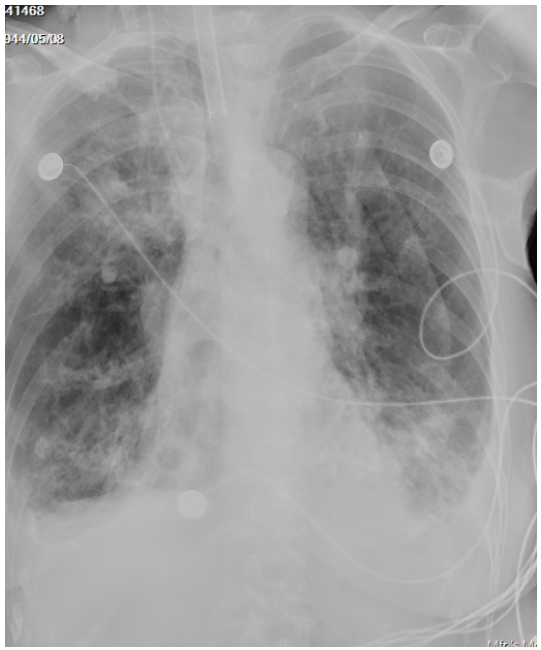

5月11日复查胸片示两下肺感染加重(图6)

图6  复查胸片(2024-05-11)